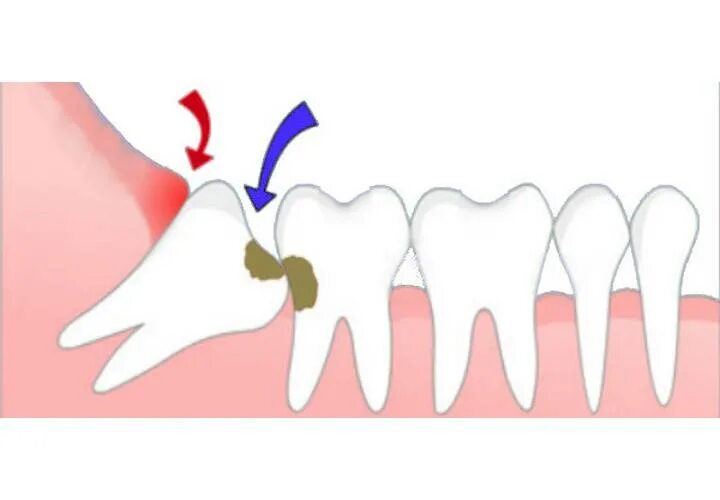

Удалить зубы семерки